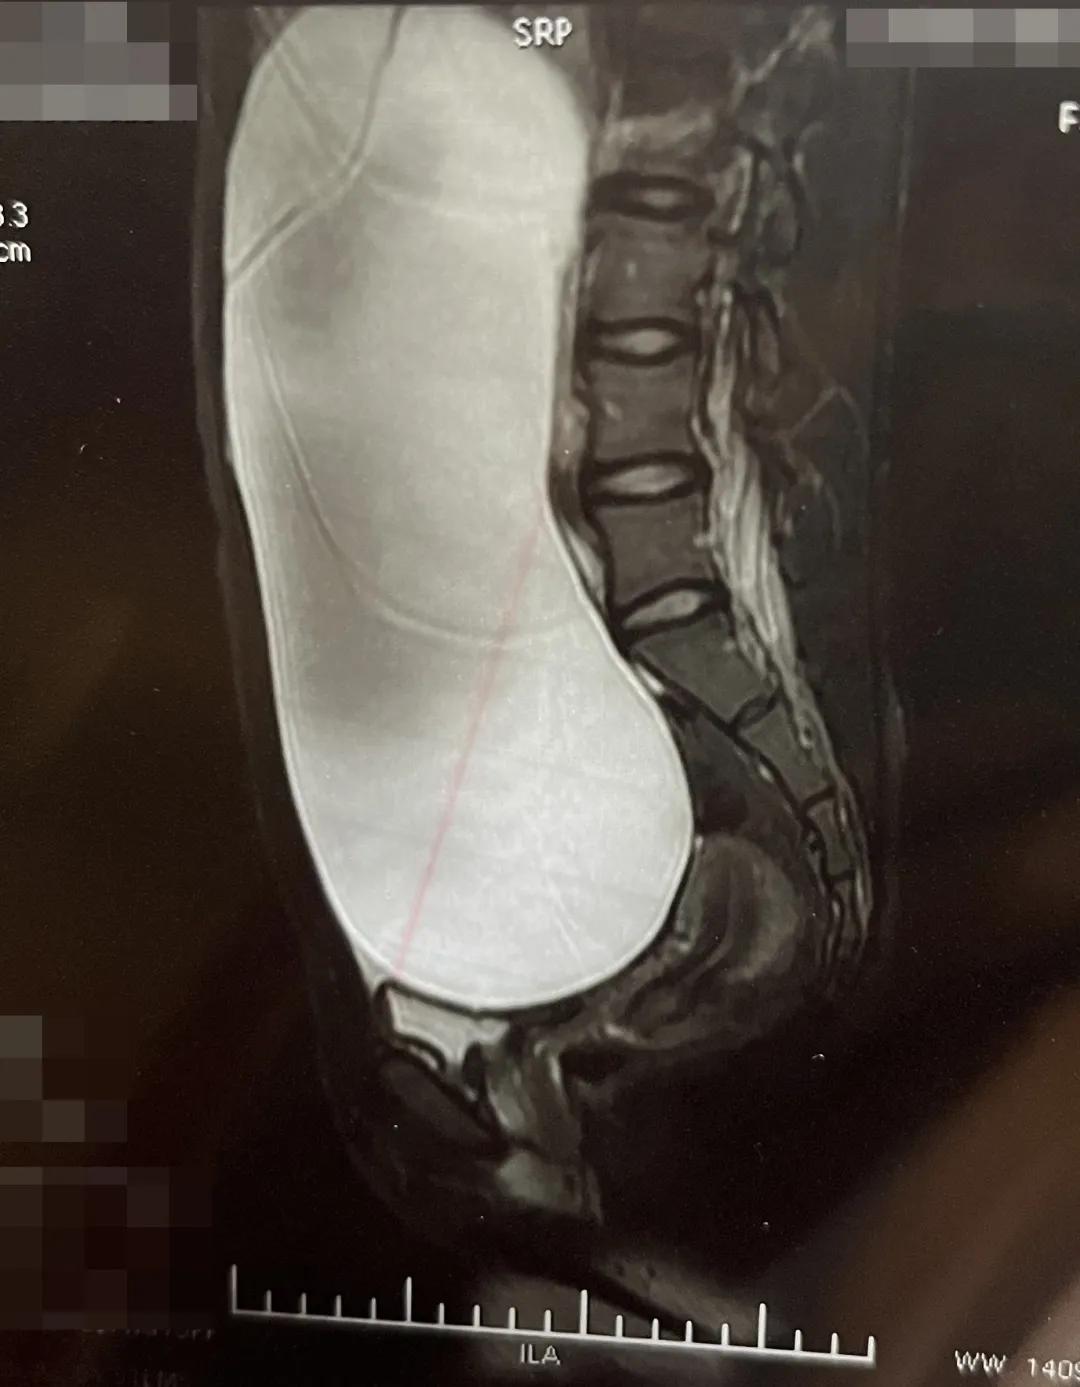

入院后,医生进一步安排了核磁共振检查。检查过程中,医生一边扫描一边调整我的位置,然而纵使我在舱内被移来移去,仍然看不清囊肿的全部边缘和细节。 核磁共振片子上,我整个腹盆腔被囊肿填满,邻近器官全部被挤向四周 ,相比囊肿,这些器官的个头显得小小的。

核磁共振图像丨作者供图